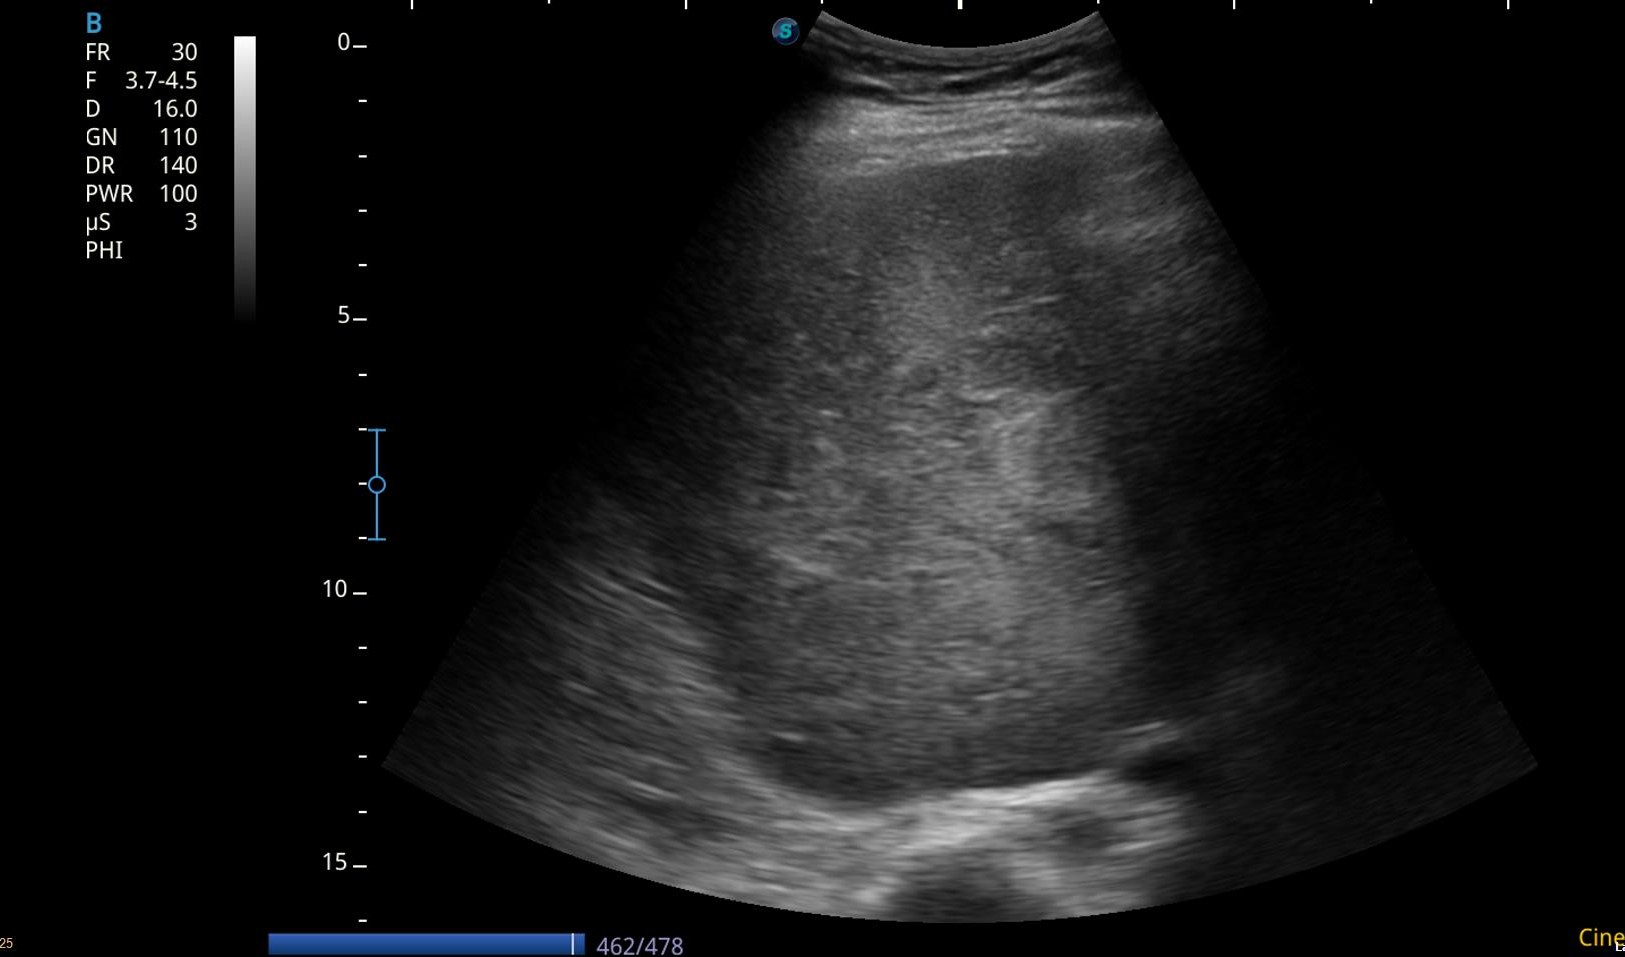

Debido a la alteración analítica se realiza una ecografía abdominal en la consulta.

Hallazgos ecográficos

Eco abdomen: Hígado de tamaño normal, nódulo en LHI de 2 cm y una gran masa heterogénea mal definida de unos 10 cm.

Resto dentro de la normalidad.